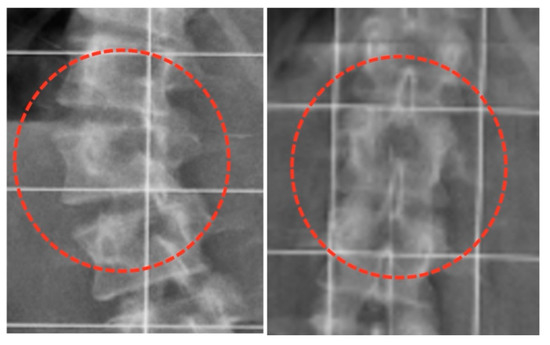

3.5. Quality of Life